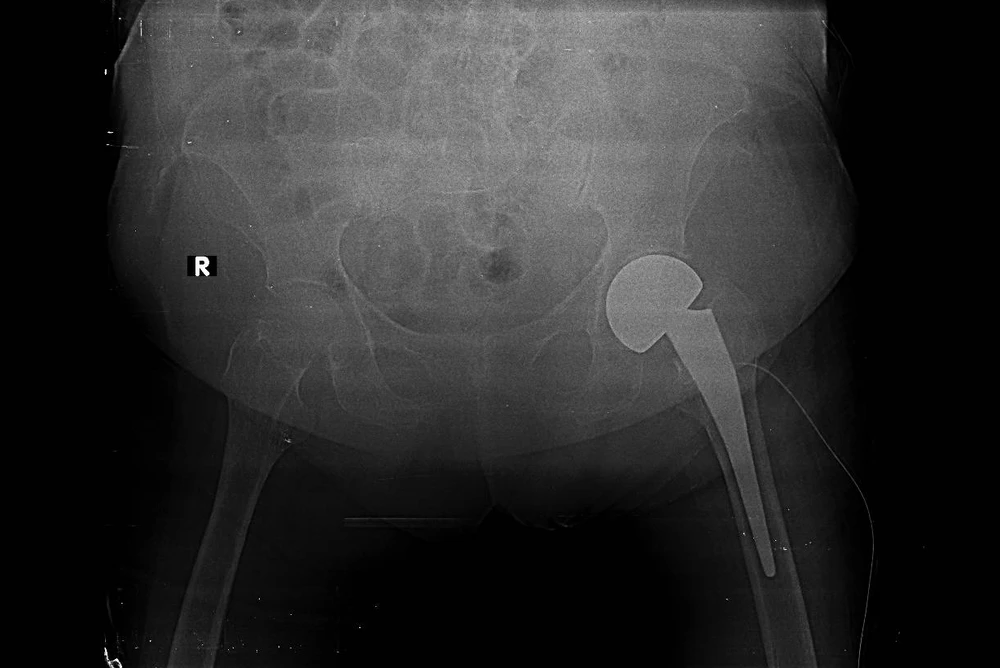

Hình X-quang khớp háng của người bệnh sau phẫu thuật. Ảnh: BVCC

Theo PGS-TS-BS Bùi Hồng Thiên Khanh, Trưởng khoa Chấn thương chỉnh hình BV ĐHYD, đây là một trong những trường hợp người bệnh cao tuổi nhất tại Việt Nam được thực hiện cả phẫu thuật thay khớp háng và khớp gối. Trước đây, những phẫu thuật lớn như thế này thường được chống chỉ định đối với người lớn tuổi vì có nguy cơ xảy ra nhiều tai biến và biến chứng trong, sau quá trình phẫu thuật.